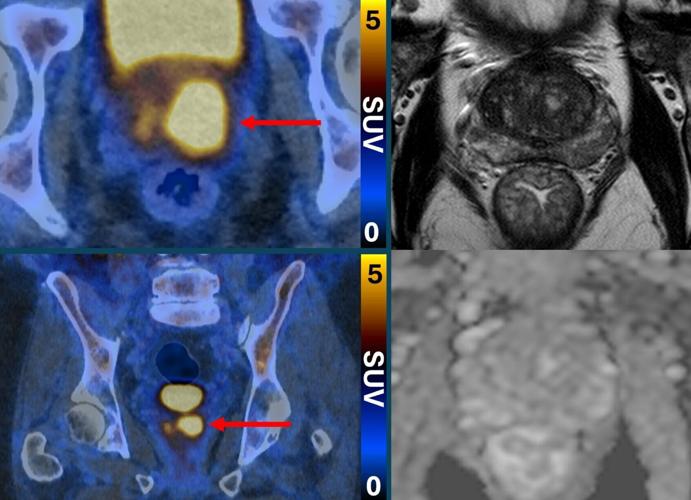

Clinically significant prostate cancer (left, PSMA PETCT) despite normal MRI (right, MRI). (PRIMARY2 via SWNS)

Primary2 found that PSMA PET/CT scanning could identify people who either did not have cancer, or whose cancer was so low-risk or slow-growing it would likely never cause harm.

Patients with a positive PSMA PET/CT scan result had a biopsy.

Researchers say the approach halved the number of pateints who needed a biopsy, without missing any harmful cancers.